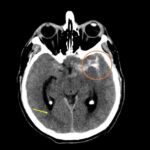

Fig. 1. TC de cerebro sin contraste: corte axial, evidenica HSA Fisher IV, Mayor espesor de HSA con hematoma asociado a nivel del valle Silviano izquierdo (circulo naranja). Volcado hemático ventricular en astas posteriores de ventrículos laterales (ver flecha).

Fig. 2. TC de cerebro sin contraste post tratamiento: corte axial, evidenica artefacto metalico por material de embolización a nivel del valle Silviano izquierdo (circulo naranja).